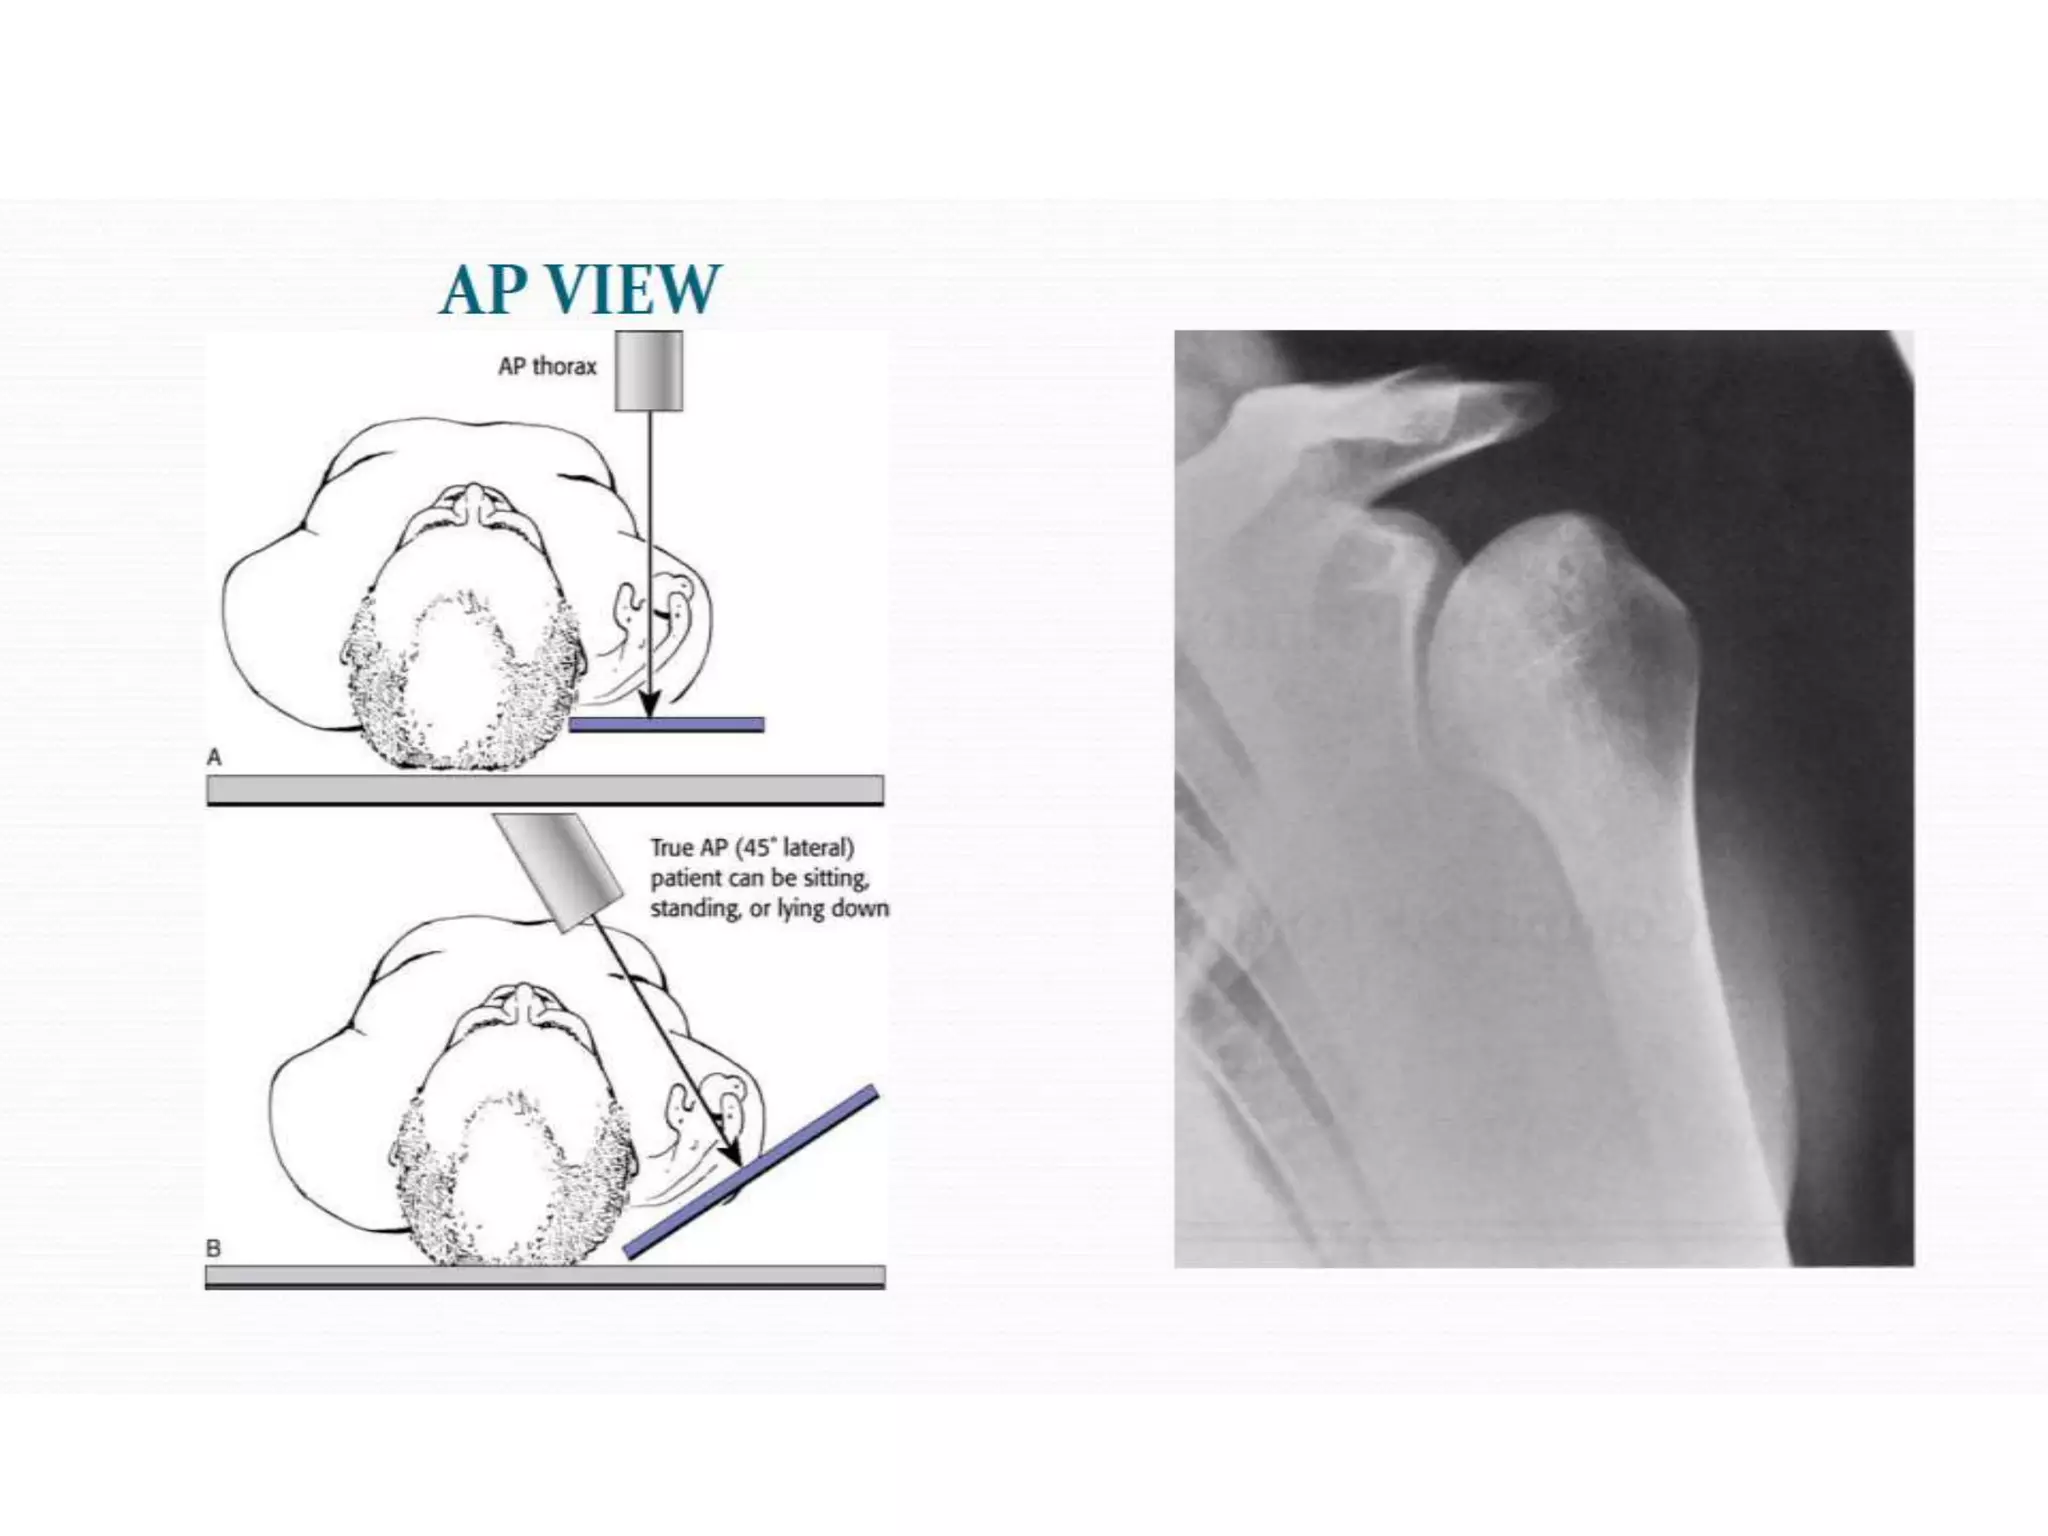

• #46 The initial radiographic examination should include anteroposterior and axillary lateral views of the shoulder. If the initial radiographic evaluation is inconclusive, special views, gadolinium-enhanced MRI, or CT arthrography can be used to show posttraumatic changes not otherwise detected.

• #49 The most common special views that can be obtained in the office are the anteroposterior view of the shoulder in internal rotation, the West Point or Rokous view, and the Stryker notch view. An anteroposterior radiograph of the shoulder in internal rotation often shows a Hill-Sachs lesion that may not be apparent on routine views.